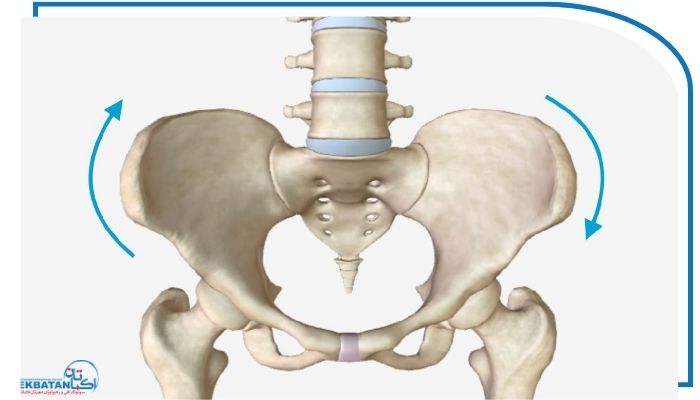

انواع چرخش لگن

انحراف پلویک زمانی رخ می‌دهد که استخوان‌های لگن از تراز طبیعی خود نسبت به ستون فقرات یا استخوان ران خارج شوند. این وضعیت ممکن است به سه شکل اصلی دیده شود که هرکدام ویژگی‌ها علائم و علت‌های خاص خود را دارند.

انحراف پلویک به طرفین (Lateral Pelvic Tilt)

در این وضعیت لگن به سمت راست یا چپ متمایل می‌شود و بدن از تعادل خارج می‌گردد. معمولاً علت آن استفاده نابرابر از پاها اسکولیوز خفیف ستون فقرات یا ایستادن طولانی با تکیه بر یک پا است. افرادی که دچار این حالت هستند معمولاً احساس می‌کنند یکی از پاهایشان کوتاه‌تر از دیگری است یا در هنگام راه رفتن بدنشان به یک سمت متمایل می‌شود. علاوه بر این درد در مفصل ران تفاوت در ارتفاع شانه‌ها و احساس عدم تقارن در لگن از دیگر نشانه‌های رایج در این نوع انحراف است.